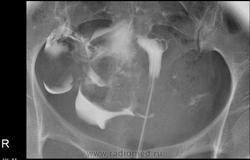

С учетом представленных нескольких снимков по интервалу времени, а следовало делать отсроченный, складывается впечатления о дефекте наполнения контрастного вещества дна матки, да и левая труба четко не законтрасирвона и контраста нет свободно распределяющегося в брюшной полости, из этого следует делать вывод по Вашим снимкам либо это следствие наличие пузырьков воздуха(а перед исследованием врач-гинеколог выпускет свободный воздух в шприце с контрастным веществом), либо это следствие образования матки или яичника и минимум после Вашего исследования надо проводить УЗИ-малого таза.

В заключении написала, что левая труба непроходима. Дефект наполнения посчитала за воздух, такую картину вижу уже не в первый раз. УЗИ сделано несколько раз перед исследованием (в разные дни цикла), без патологии.

Исследование проведено с нарушениями: воздуху в полости матки абсолютно нечего делать, эта воздушная пробка могла стать причиной отсутствия контрастирования левой трубы, так что диагностическое значение исследования снижено. Экстравазация тазовых вен ни о чем плохом не говорит. Картина распределения контаста в правой половине малого таза - тоже без патологии.

Интравазация околоматочных сосудов. Подобные наблюдения демонстрировались на сайте. Надеюсь всё прошло без санитарных потерь?